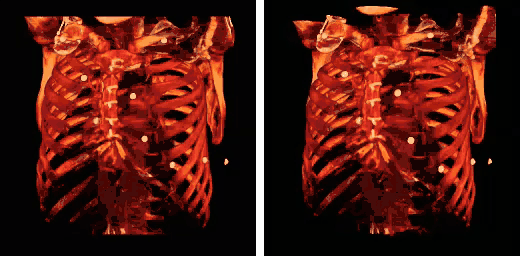

The four floating ribs indicated

The eleventh and twelfth ribs, the floating ribs, have a single articular facet on the head, which is of rather large size. They have no necks or tubercles, and are pointed at their anterior ends. The eleventh has a slight angle and a shallow costal groove, whereas the twelfth does not. The twelfth rib is much shorter than the eleventh rib, and only has a one articular facet.[8]